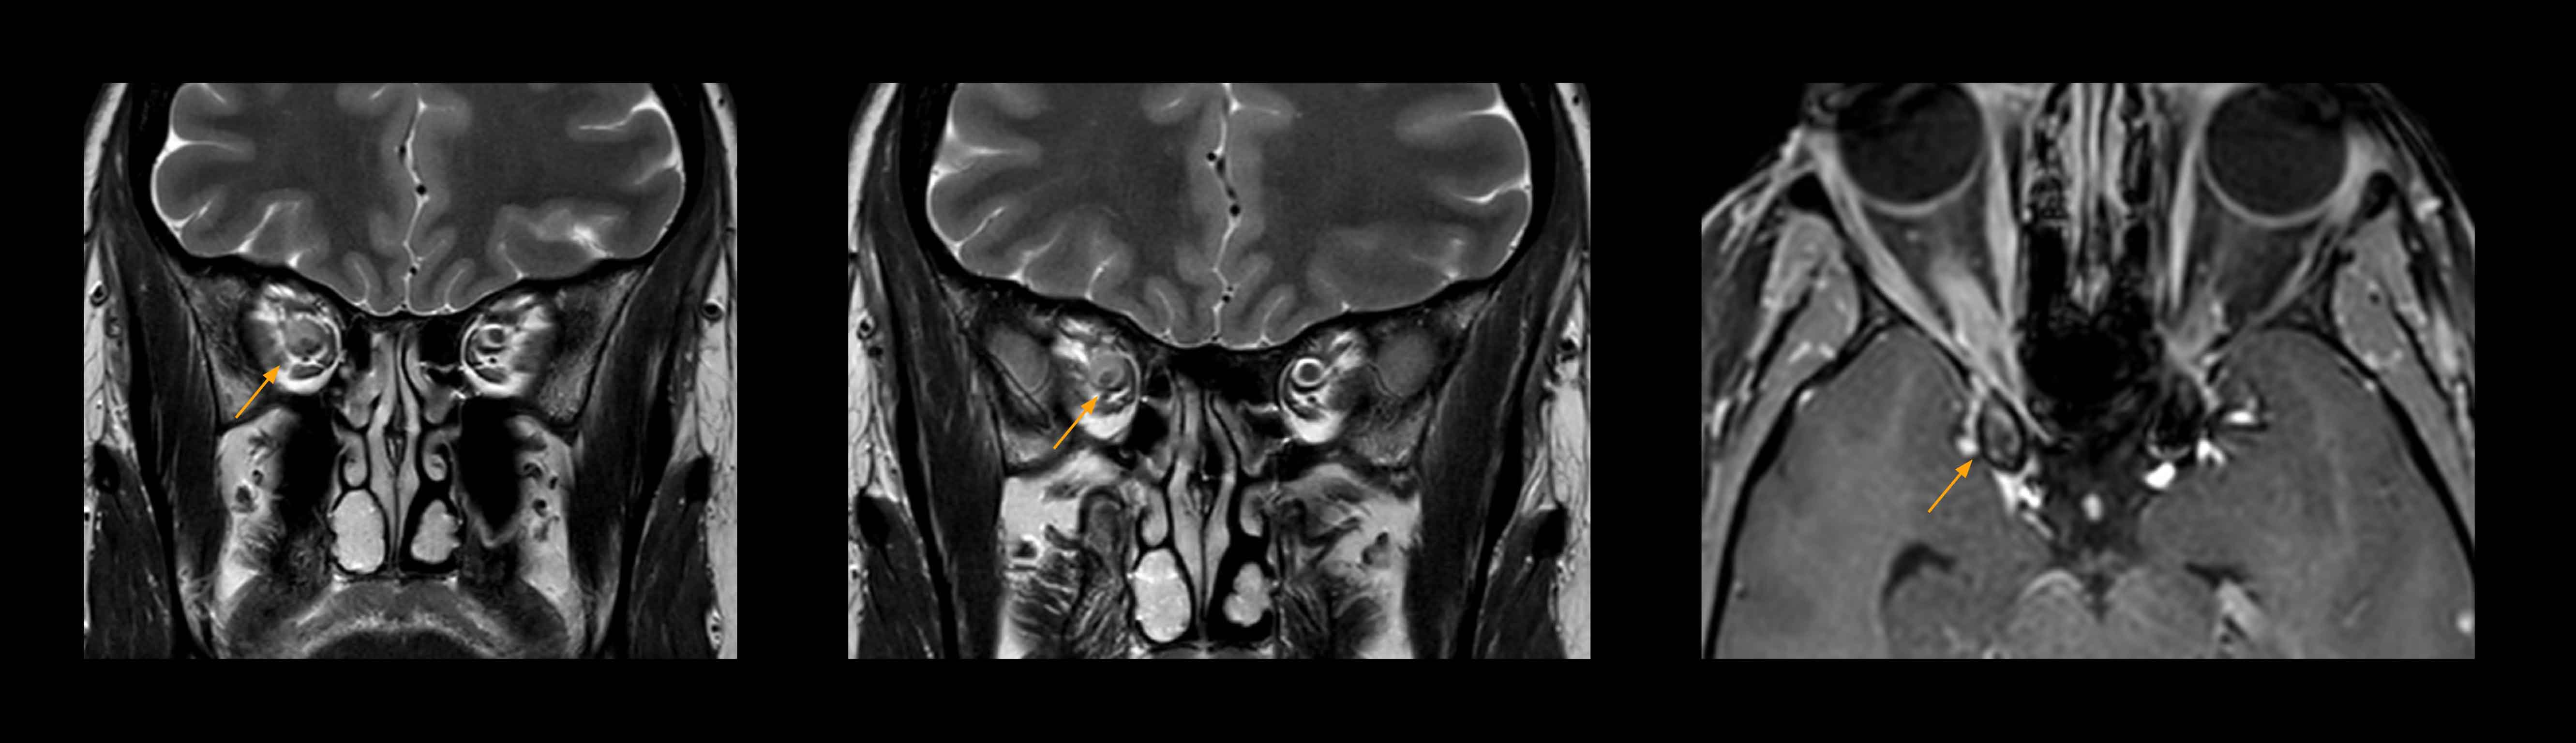

High-resolution MRI impressively demonstrates the compression and narrowing of the right optic nerve in this case of optic nerve sheath meningioma (ONSM). The coronal T2-weighted images show the hyper-intense, half-moon shaped lesion, that is clearly visible in the axial T1W image after contrast injection (right). These imaging findings were so convincing that there sponsible neurosurgeon did not consider a pretherapeutic histological clarification.

High resolution-MRI impressively demonstrates the compression and narrowing of the right optic nerve in this case of optic nerve sheath meningioma (ONSM). The coronal T2-weighted images show the hyper-intense, half-moon shaped lesion, that is clearly visible in the axial T1W image after contrast injection (right). These imaging findings were so convincing that there sponsible neurosurgeon did not consider a pretherapeutic histological clarification.